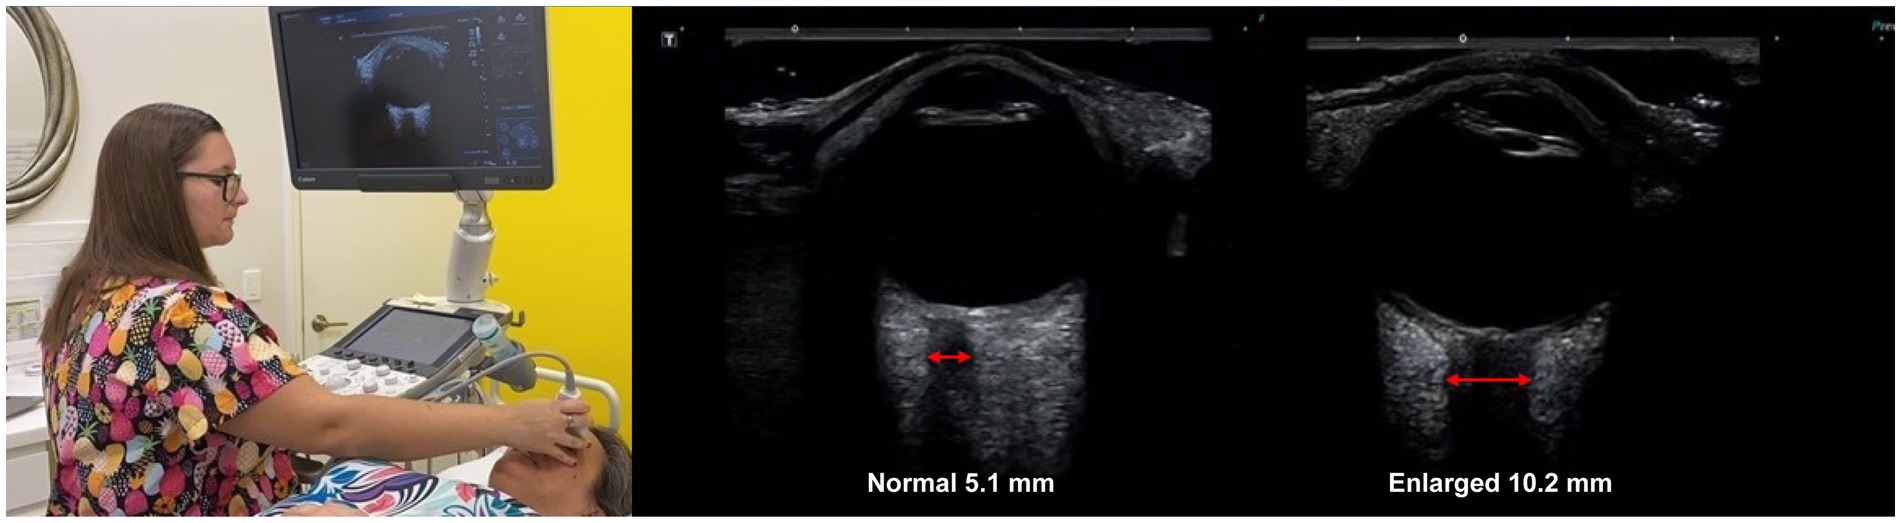

All patients went through neck vitals analysis by a medical ultrasonographer, which included cervical and ocular ultrasounds and measurements of the vagus nerves’ cross-sectional area (CSA) mid-neck, IJV CSA in the supine position at C4-C5 and C1 (Canon Aplio a550 ultrasound with 7 MHz linear probe), pupil diameter and light reflex (NeurOptics NPi®-200 pupillometer), IOP (iCare ic200 tonometer), and ONSD (Canon ultrasound, ocular setting) (see Figure 3).

Ultrasound ONSD measurement is a valid noninvasive imaging technique to detect and monitor intracranial hypertension, as the optic nerve is surrounded by CSF through the subarachnoid space (55–58). The optic nerve emerges from the posterior part of the globe and appears as a hypoechoic linear structure with a hyperechoic border (nerve sheath). The outer rim should be included in optic nerve sheath measurements and should be measured 3 mm behind the posterior rim of the globe (where standard measurements are made.) Measurements in healthy adults are generally between 4.9–5.3 mm (59). Emergency rooms and others consistently use an ONSD measurement greater than 6.0 mm to diagnose intracranial hypertension, though some use an even lower cut-off (60–64) (see Figure 9).